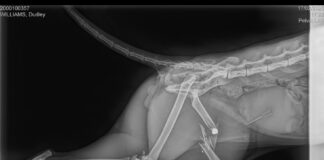

Cat’s leg amputated following air gun attack which shatters hip –...

RSPCA Cymru has launched an appeal for information

RSPCA Cymru is appealing for information after a much-loved pet cat was shot with an air gun...